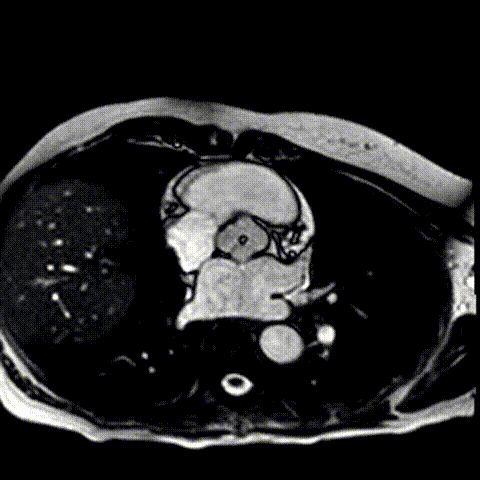

此外,心脏磁共振排除了其他先天性异常,并计算出主动脉反流分数为35%(图D,视频S3)。左心室射血分数为62%,但存在心腔扩张(左心室收缩末期内径47 mm,舒张末期容积指数101 mL/m²)。

(图D)心脏MRI。